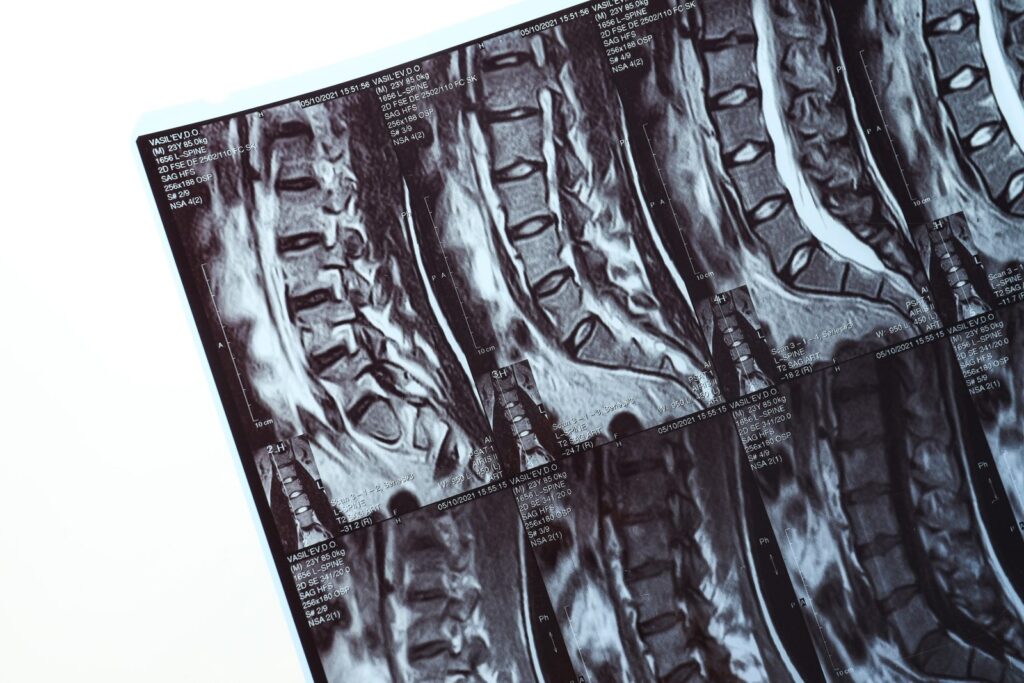

A ressonância magnética utiliza um campo magnético e ondas de rádio para criar imagens de alta definição das estruturas internas do corpo. Diferentemente do raio-X e da tomografia computadorizada, que são mais eficazes para visualizar ossos, esse exame se destaca na análise de tecidos moles, como:

A ressonância magnética é recomendada para uma ampla variedade de condições ortopédicas, incluindo:

A ressonância magnética é, sem dúvida, o padrão ouro para diagnósticos ortopédicos devido à sua precisão, segurança e capacidade de detectar alterações em tecidos moles que outros exames não conseguem identificar.

Seja para diagnosticar lesões, planejar cirurgias ou monitorar tratamentos, esse exame é uma ferramenta indispensável na ortopedia moderna.